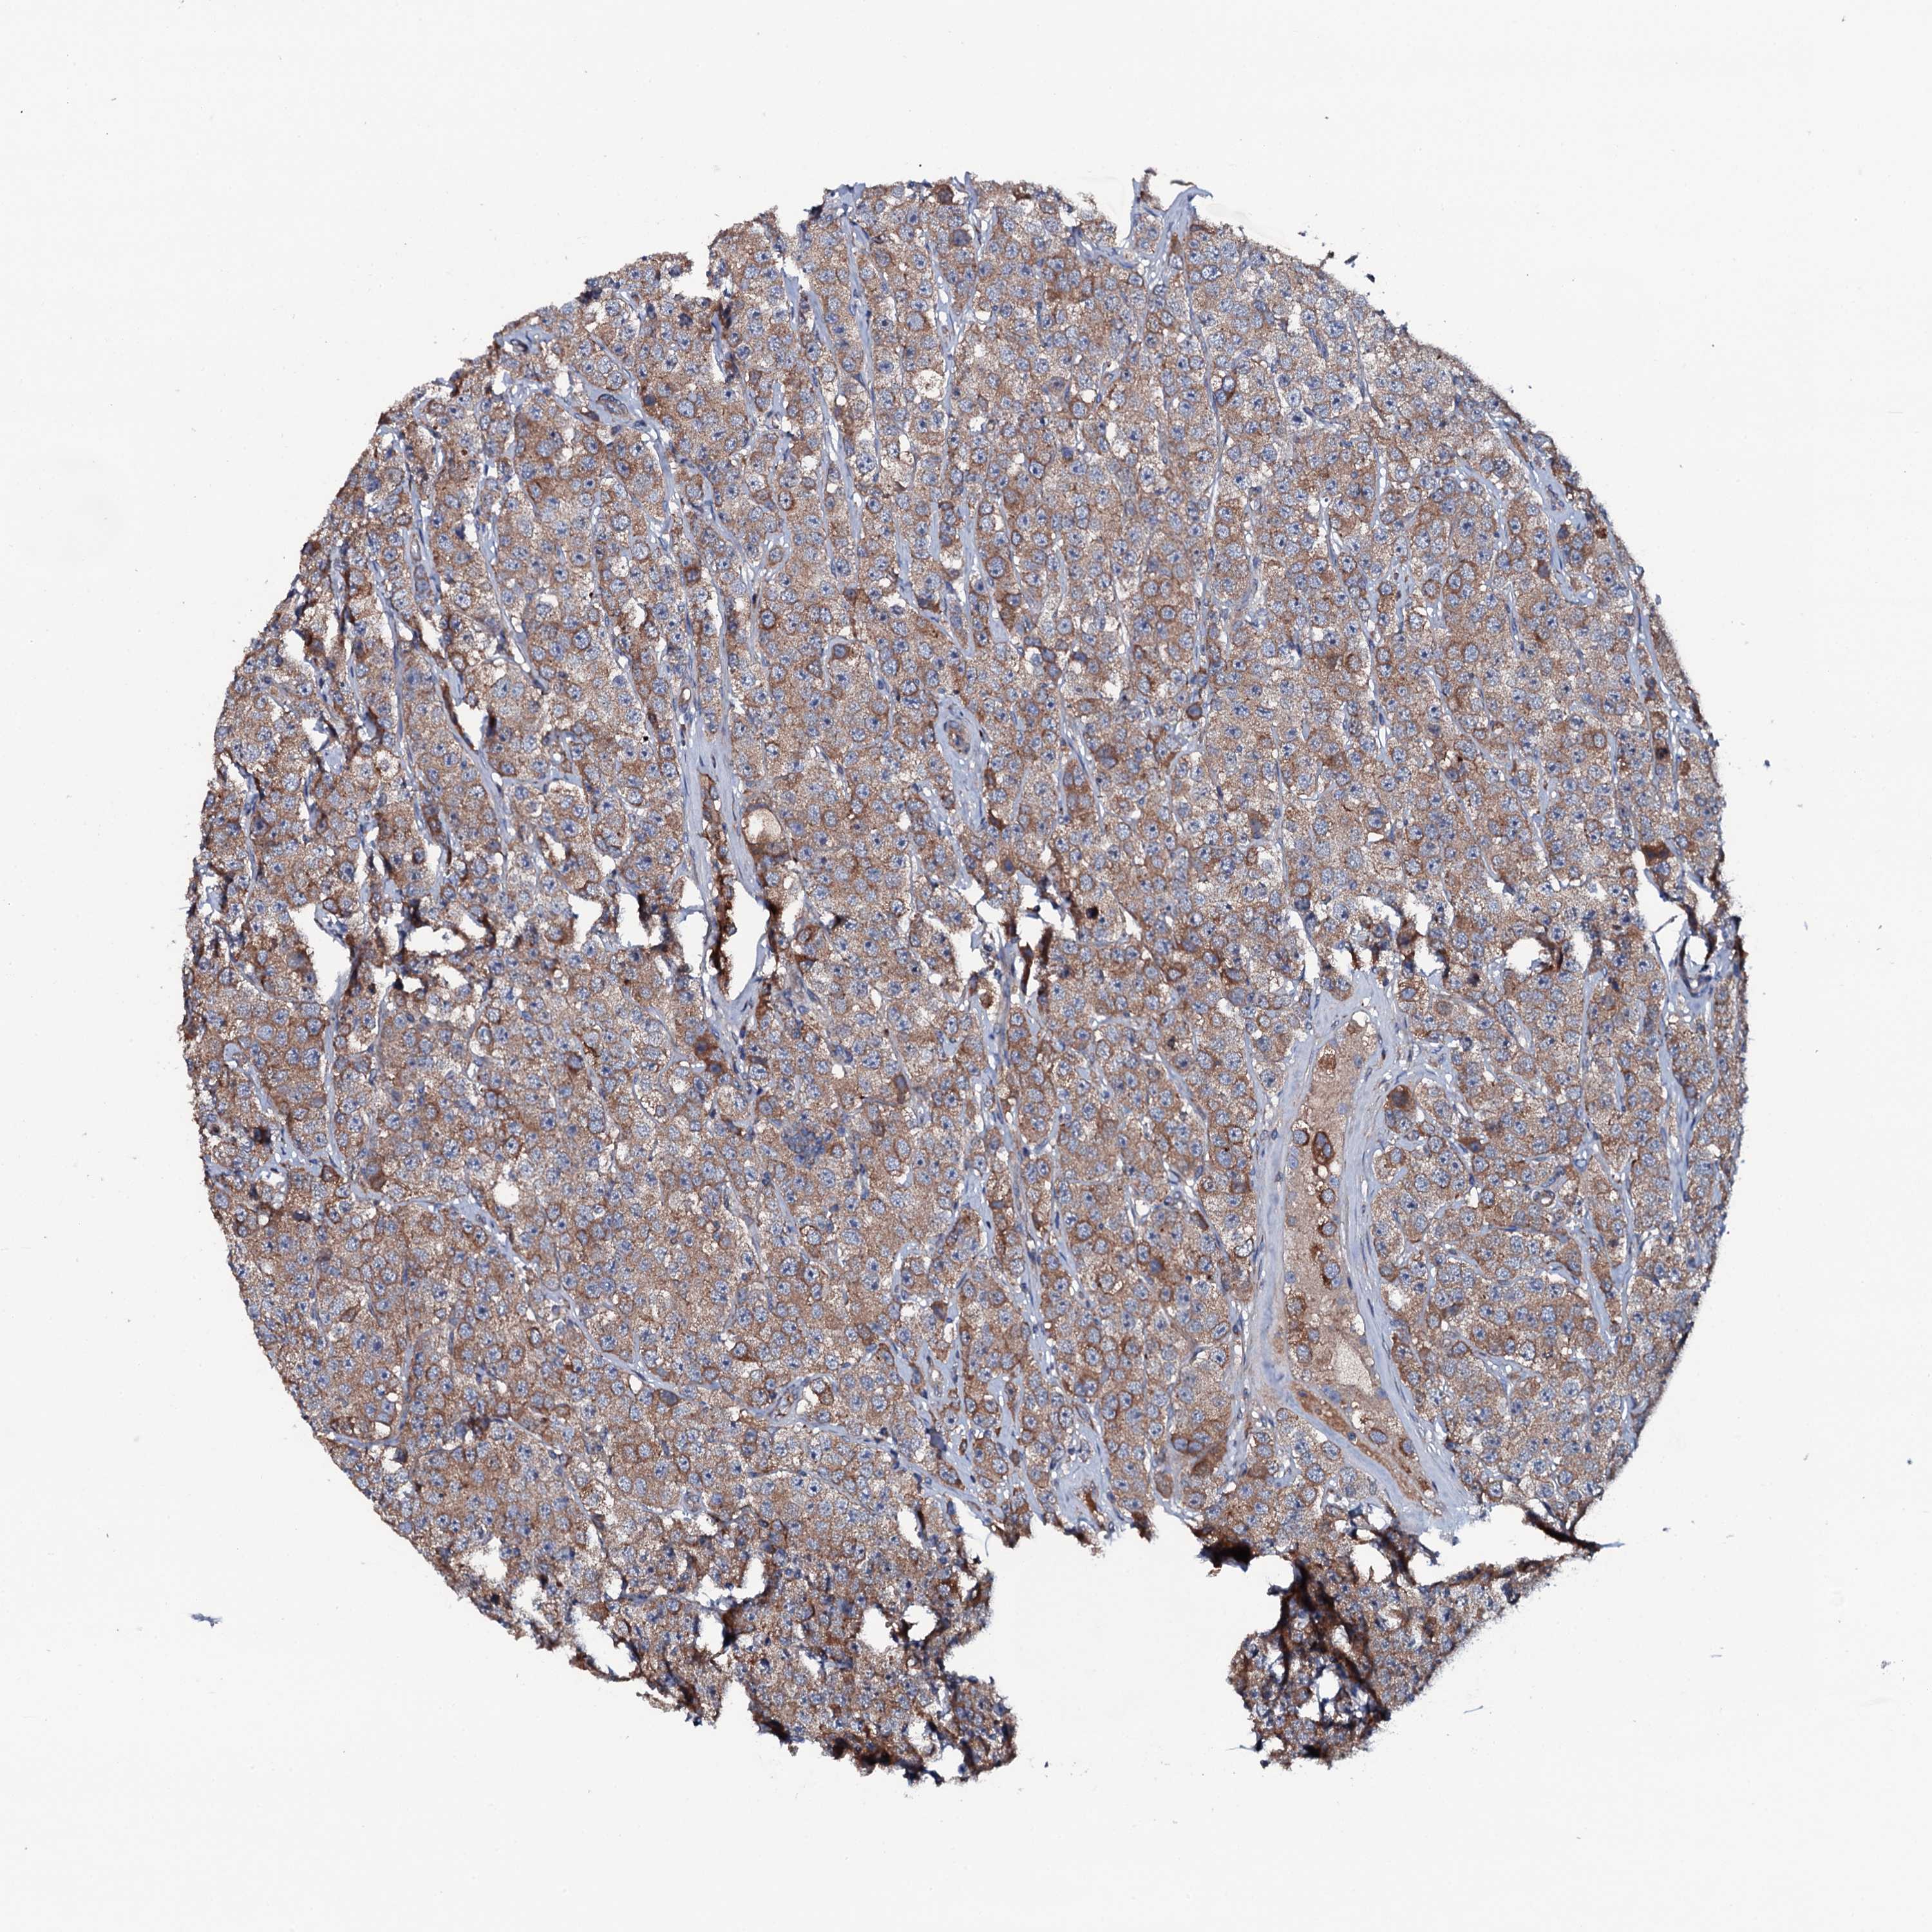

TESTIS CANCER - Protein expressioni

A mouse-over function shows sample information and annotation data. Click on an image to view it in a full screen mode. Samples can be filtered based on level of antibody staining by selecting one or several of the following categories: high, medium, low and not detected. The assay and annotation is described here.

Note that samples used for immunohistochemistry by the Human Protein Atlas do not correspond to samples in the TCGA dataset.

Antibody stainingi

Antibody staining in the annotated cell types in the current human tissue is reported as not detected, low, medium, or high, based on conventional immunohistochemistry profiling in selected tissues. This score is based on the combination of the staining intensity and fraction of stained cells.

Each image is clickable and will lead to virtual microscopy that enables deeper exploration of all samples and also displays staining intensity scores, fraction scores and subcellular localization as well as patient and tissue information for each sample.

Antibody HPA020873

Antibody HPA040413

Carcinoma, Embryonal, NOS

Seminoma, NOS

Urothelial carcinoma, High grade